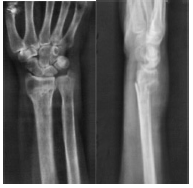

ճաճանչոսկրի դիստալ մետաէպիֆիզի տեղաշարժված կոտրվածք

Կոնտրոլ` համադրումից հետո

Երկրորդային տեղաշարժ 7-10 օր անց

ճաճաևչոսկրի դիստալ Մետաէպիֆիզի տեղաշարժված կոտրվածք

Կոևտրոլ`դիաֆիքսացիայից հետո